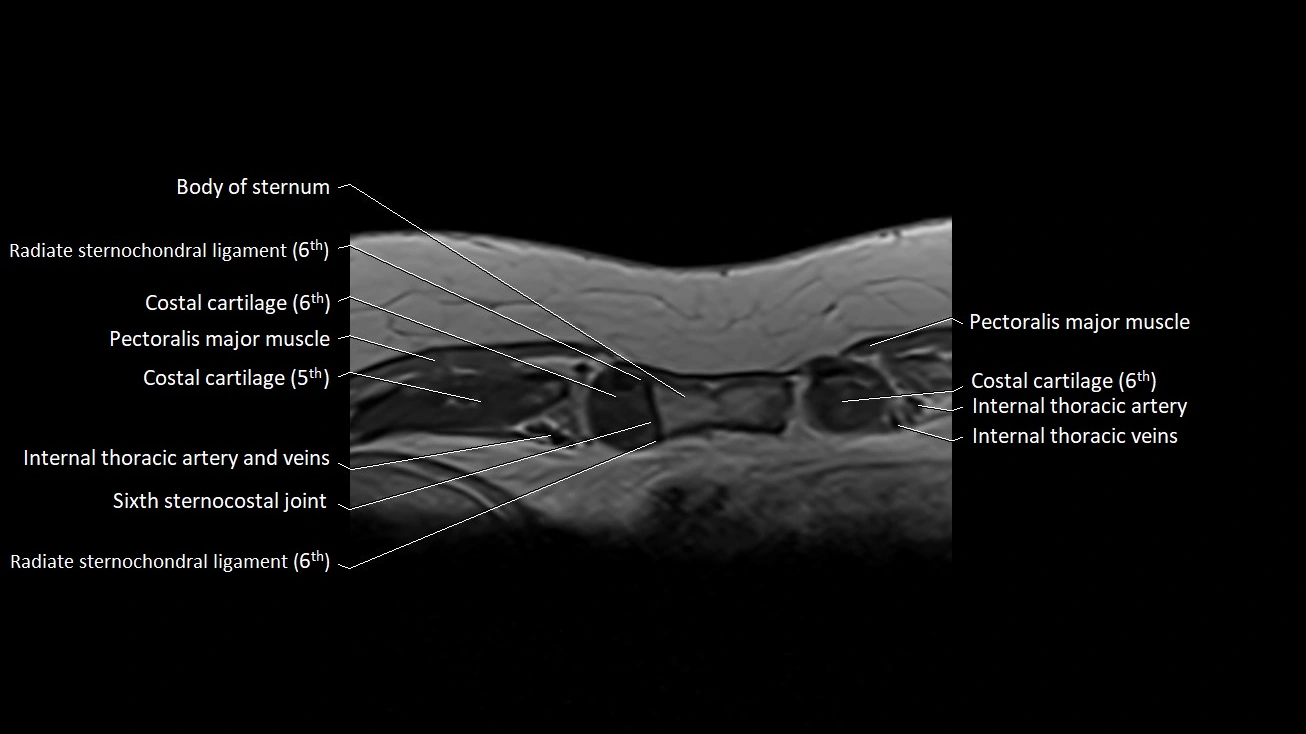

MRI images

image